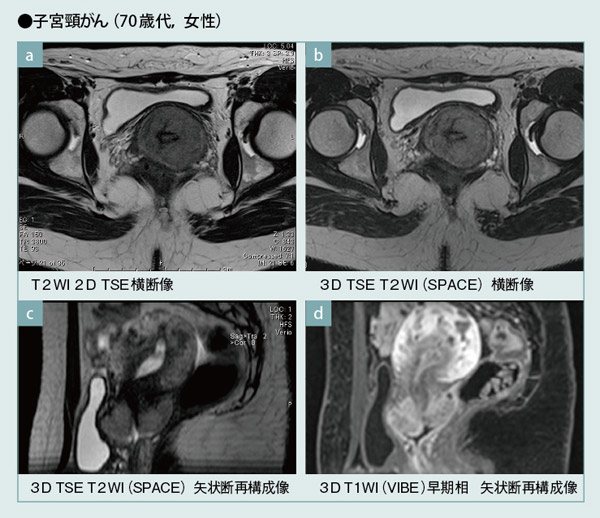

3D SPACE(b)は,従来の2D T2強調像(a)と同様のコントラストの画像をiso voxel imageで得ることが可能である。任意断面の画像(c)を再構成で作成することが可能であり,腫瘍の広がり診断に必要な情報を1回の撮像から得られる。

iso voxel 3D T1強調像(VIBE)によるdynamic MRI(d)は,任意断面の再構成ができるため,造影前に撮像断面の選択に悩むことがなく,検査担当者の負担も軽減できる(本症例は,横断像で撮像している)。